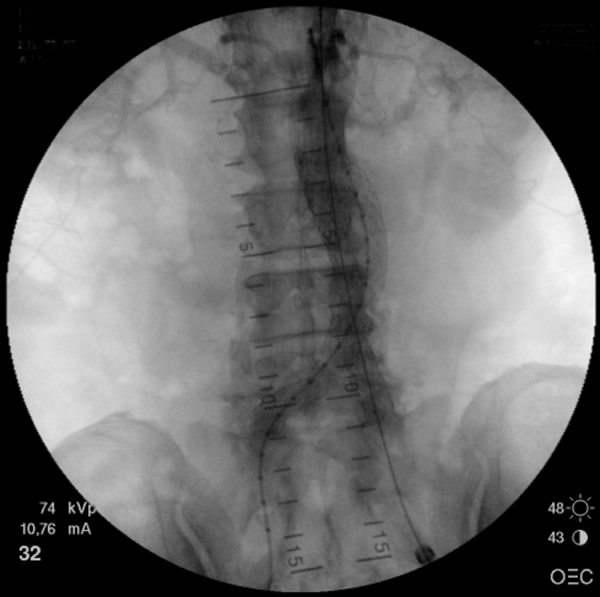

- The main trunk is flushed with heparinized solution, advanced into the proximal neck, positioned just inferior to the lowest renal artery, and oriented so that the contralateral limb gate can be easily accessed. The orientation of the contralateral gate is performed using the manufacturer’s radiopaque markers at the crown of the trunk and/or the stent graft bifurcation under fluoroscopic guidance. A repeat angiogram is commonly performed to reconfirm the positioning of the device within the aorta. Subsequently, the main trunk is deployed (Figures 2, 3), opening the contralateral limb gate.

Figure 5: The stent graft is completely deployed and ballooned. Angiogram reveals patent bilateral renal and internal iliac arteries.